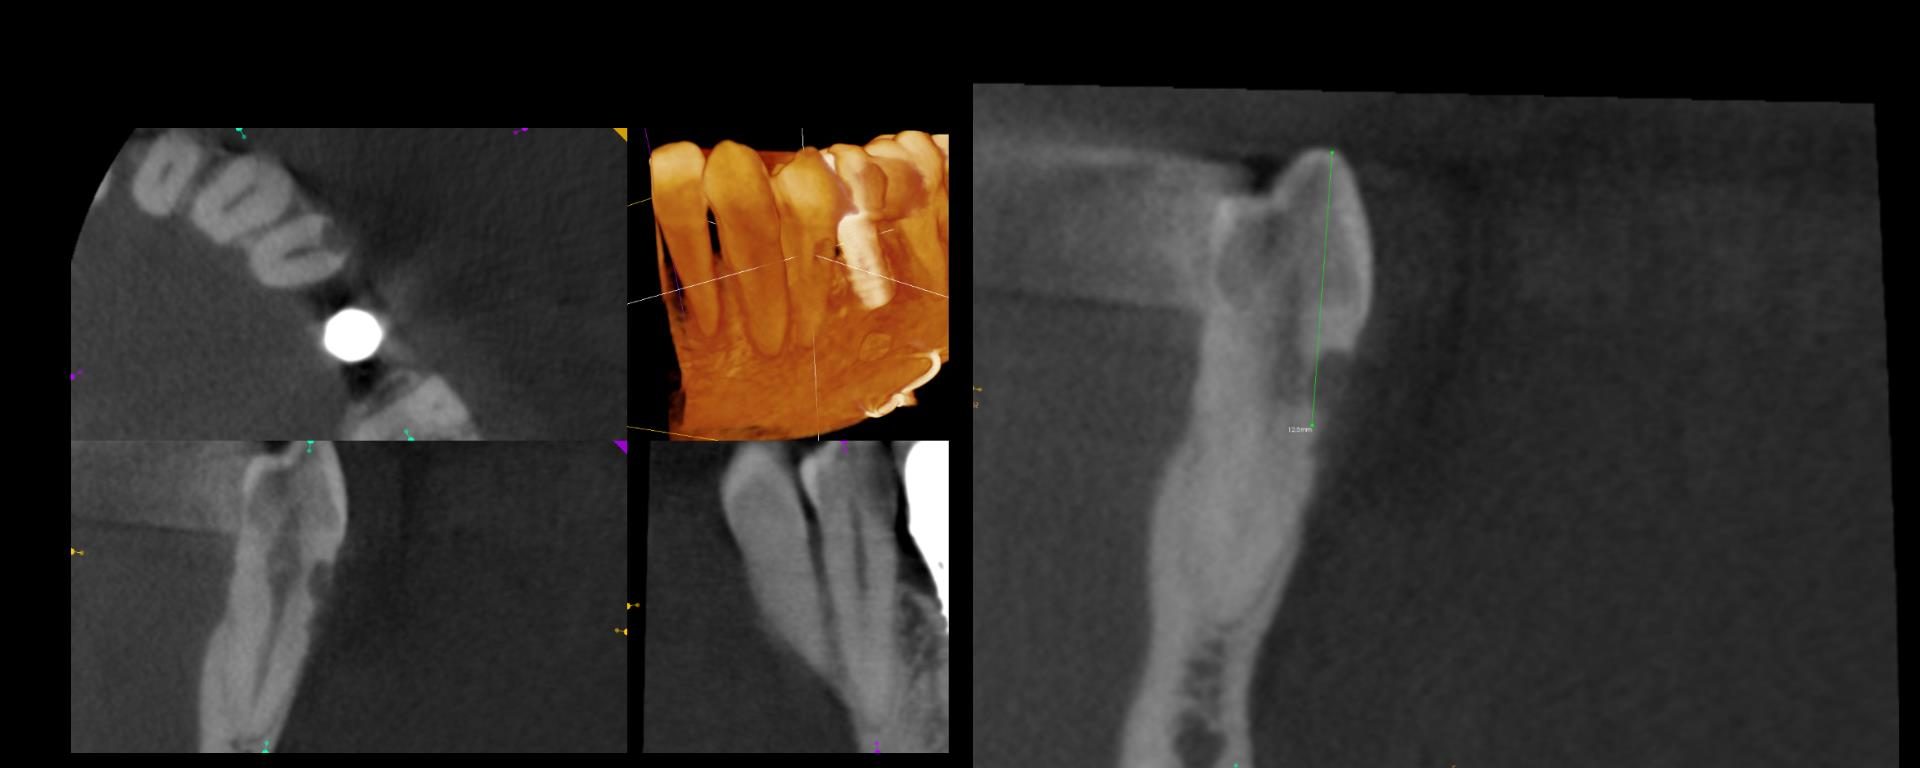

5 yr CBCT recall

July 24, 2018 0 comments

Entire buccal plate missing. CBCT at 5 years suggests most, but not all, bone has regenerated. As canine bridge abutment, it is subjected to some occlusal trauma. gbc